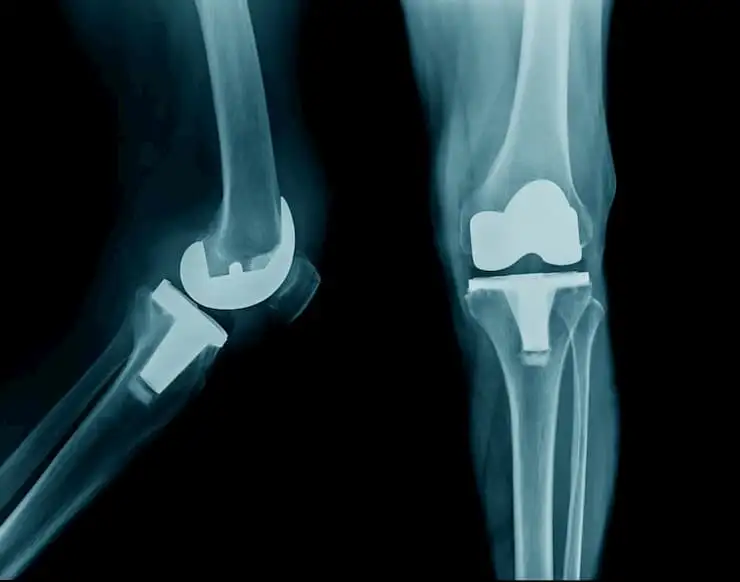

Efficacy of co-treatment with oral Duloxetine and intraarticular injections for knee osteoarthritis

A prospective, randomized, open-label research was carried out to determine the usefulness of combination of Duloxetine and injections of hyaluronic acid (HA) and corticosteroid (CS) in osteoarthritis of the knee.

In people suffering from osteoarthritis of the knee, using oral Duloxetine along with intraarticular injection of corticosteroid + hyaluronic acid is effective to improve pain and knee function.

Co-treatment with Duloxetine and intraarticular (HA+CS) injections elicited remarkable pain relief and improved knee function when compared to intraarticular injections alone.